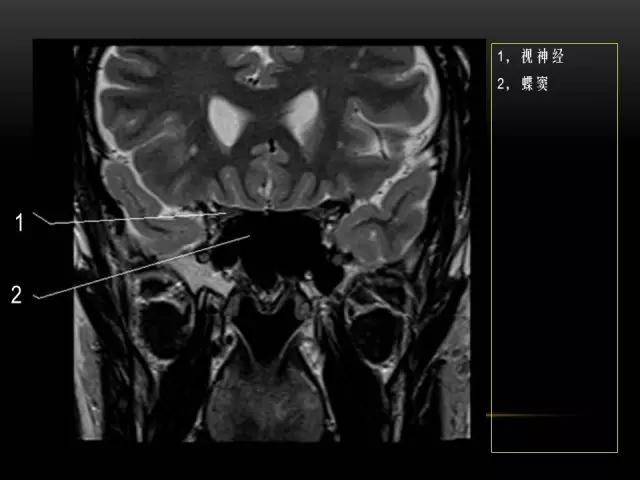

下文是在MRI下眼部及鼻窦的冠状位解剖图谱。